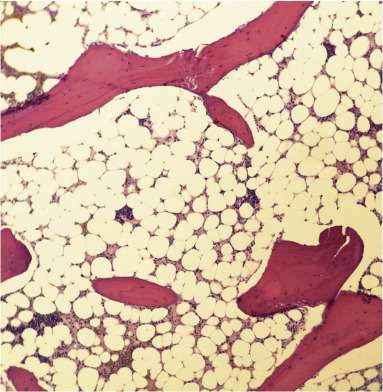

La aspiración de médula ósea y la biopsia de médula ósea son procedimientos diagnósticos cruciales en la evaluación de la anemia aplásica. En estos estudios, la médula ósea aparece hipocelular, lo que significa que hay una notable escasez de células hematopoyéticas, y la cantidad de precursores hematopoyéticos morfológicamente normales es escasa. Esto contrasta con la médula ósea normal, que tiene una alta proporción de células madre y precursores de todas las líneas sanguíneas. La hipocelularidad es un hallazgo característico en la anemia aplásica, reflejando la insuficiencia medular y la incapacidad de producir nuevas células sanguíneas.